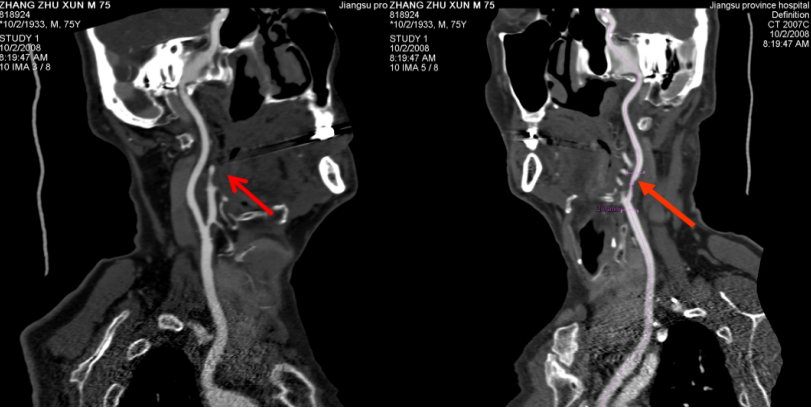

对经常“头昏、头痛”且既往无高血压疾病的患者,可提供头颈部CTA检查,从而早期发现是否有头颈部血管硬化、狭窄及畸形等问题导致头昏、头痛。

图为颈动脉CTA提示颈动脉粥样硬化斑块形成案例